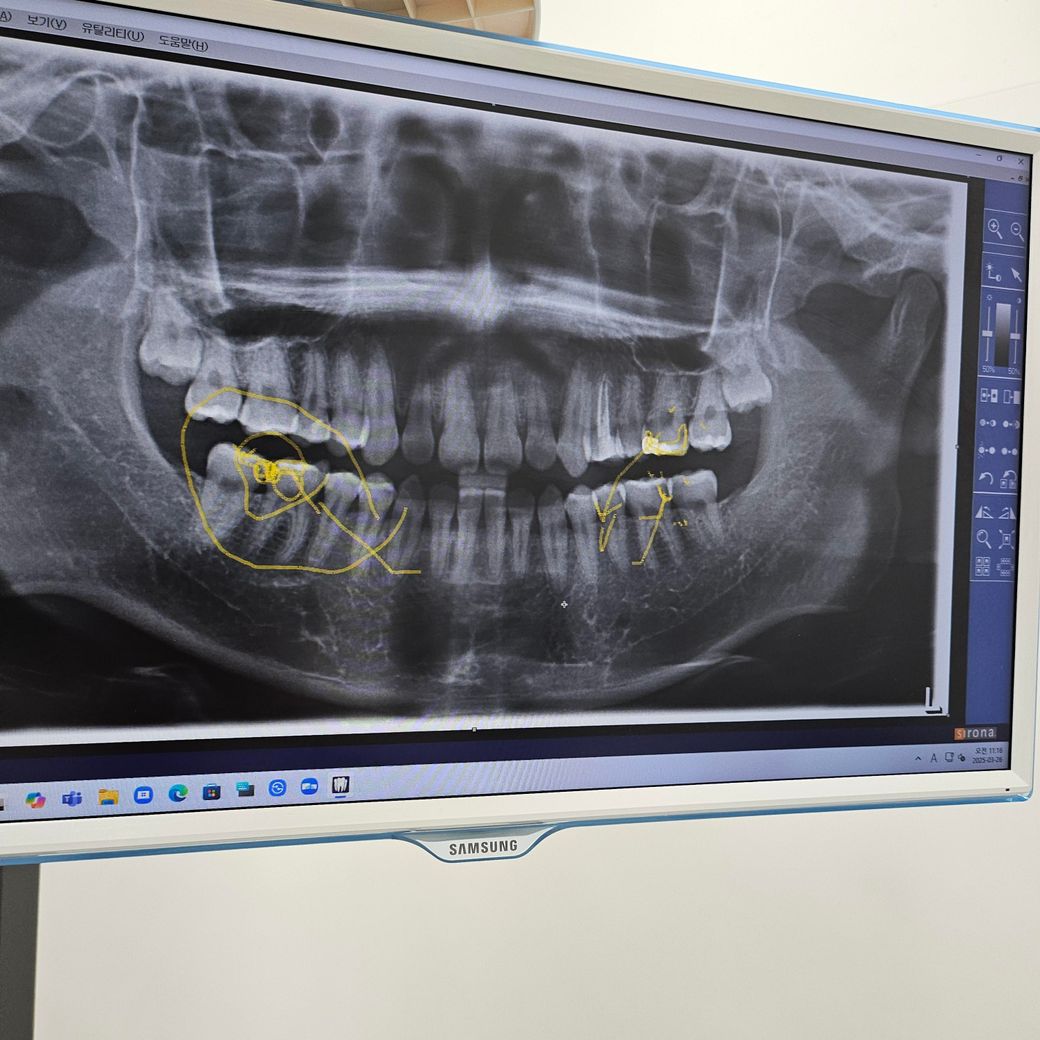

치과 충치 치료 보철치료 문의 드립니다

오늘 치과 내원하여 우측 하단 2개 이빨 인레이를 진행하고 왔습니다.

사진상 동그라미 부분을 진행후 나머지 왼쪽위 크라운

아래 치아 사이는 인레이를 추천하시더라구요.

엑스레이 상으로 충치가 많이 깊어 보이고 치아 사이도 충치가 잇는거 같습니다 .인레이나 크라운 치료를 하셔야될것같습니다.